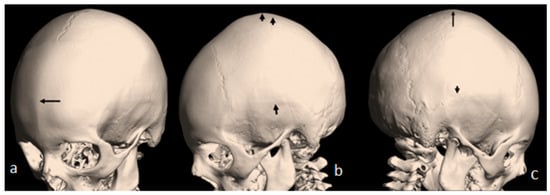

A 7-year-old boy with West syndrome associated with hyperkinetic disorder was referred to our department because of ligamentous hyperlaxity and flat foot. Clinical examination showed growth deficiency (10th percentile). Surprisingly, he manifested an abnormal cranial phenotype almost typical for his mother. Palpation of his skull showed a bony ridge over the metopic suture, associated with an unusual bulge over the mid-sagittal suture. Bilateral bony ridges over the squamosal sutures were well delineated. Palpation of his 35-year-old-mother’s skull showed a prominent bony bulge over her sagittal suture. AP skull radiograph of a 7-year-old boy with West syndrome showed facial asymmetry with early closure of the metopic suture (arrow head) similarly the coronal as well as the sagittal sutures showed post-closure sclerosis (Figure 1a). A 3D reformatted frontal cranial CT of a 35-year-old mother clearly showed the closure of the metopic (arrow) and the sagittal sutures causing a mid-sagittal bony bulge (red-arrow) (Figure 1b). A 3D reconstruction CT scan of the 7-year-old-child with mild flexion of the skull showed early closure of the metopic suture (arrow) (a). A 3D reconstruction CT scan showed early closure of the squamosal sutures (arrow), pressing the brain contents upward, causing the development of a prominent bulge at the top of the mid-sagittal sutures two arrows (Figure 2b). Another 3D reconstruction CT scan confirmed the bilateral closure of the squamosal suture (arrow head). The vertical arrow showed abnormal bulging of the vertex secondary to bilateral pressure exerted by the squamosal sutures (c).

Figure 1. (a). AP skull radiograph of a 7-year-old boy with West syndrome showed facial asymmetry with early closure of the metopic suture (arrow head) similarly the coronal as well as the sagittal sutures showed post-closure sclerosis; (b) A 3D reformatted frontal cranial CT of a 35-year-old mother clearly showed the closure of the metopic (arrow) and the sagittal sutures causing a mid-sagittal bony bulge (red-arrow).